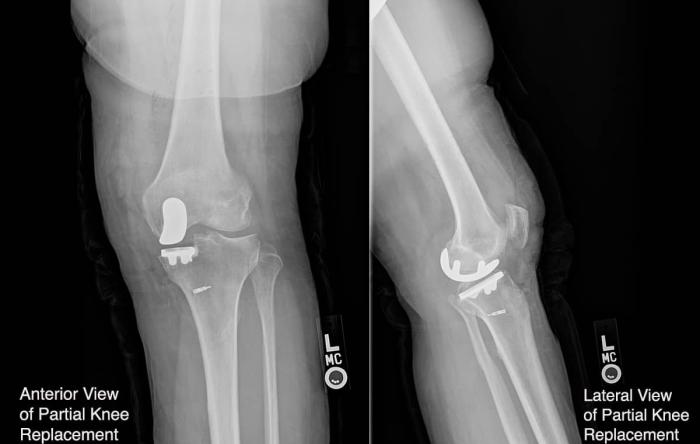

ACL surgery is performed more than 100,000 times...